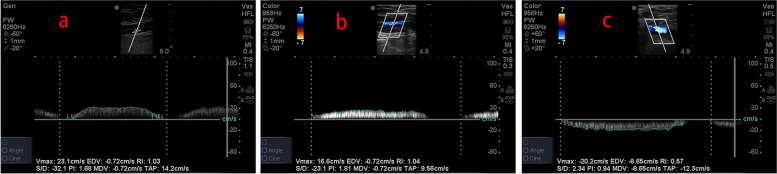

All ultrasonic assessments were performed by a skilled physician, using a Sonosite M-Turbo ultrasound system. First, the transducer was placed on the horizontal axis of the vein. We froze images for assessments of AP diameters, LM diameters, and CSA when the transducer located the ideal positions (Fig. 1). A slight flexion and rotation of the knee joint were required in order to scan the PV. In addition, all patients were in the same posture when PV was measured to avoid deviations caused by posture or additional pressure. Peak velocity and mean velocity were obtained by placing the transducer longitudinally on the vein. The Doppler sample volume cursor was positioned in the center of the venous lumen and the Doppler wave was scanned three times separately (Fig. 2). Mean value was calculated by averaging three measurements.

Fig. 2.

The Doppler sample volume cursor was positioned at the center of the venous lumen, and peak blood velocity and mean blood velocity were measured. a CFV point (proximal part of the junction of the superficial femoral vein and deep femoral vein). b GSV point (distal part of the junction of the GSV and CFV). c junction point (proximal part of the junction of the GSV and CFV)